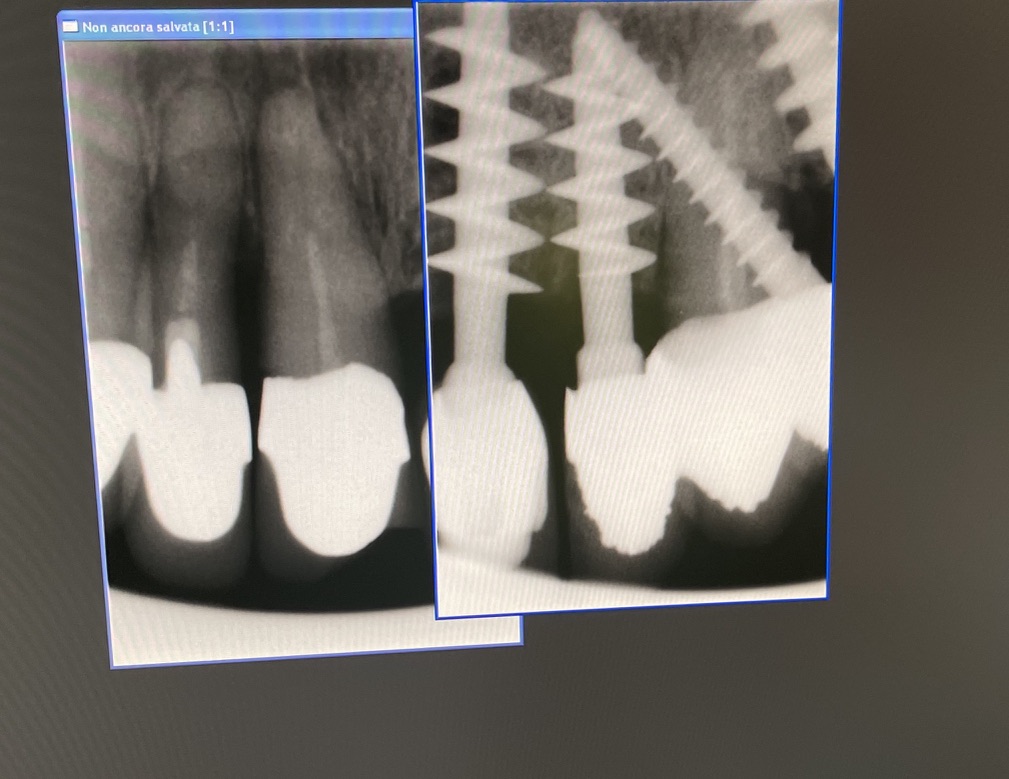

N° impianti esistenti 10

Data e n°interventi fatti: 2014:35 44 45 46. 2016: 16. 2017:22 23 24 25. 2019: 21

Tipo di impianto Tramonte

Zona dentale: 11 12

App. Rx endorale : vix win Guidizzxolo

Densità secondo Misch: D2, D3

Sequenza frese: solo lanceolata

Sequenza maschiatori: diametro 4 mm